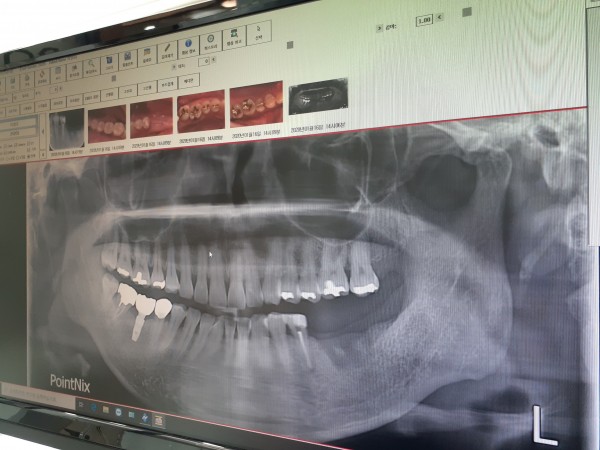

[질문] 임플란트 재수술은 어떻게 진행되나요?

[답변] 임플란트 치료가 늘어가면서 그 만큼 부작용이나 실패 사례도 늘어가고 있습니다.

임플란트 수술 후 환자의 관리가 매우 중요합니다. 수술 후 지켜야할 기본적인 사항들과 청결한 치아상태를 유지해야 하는데 이를 가볍게 여겨 제대로 된 치아관리를 하지 않으면 임플란트의 부작용이 생길 가능성이 높습니다. 또한 치과의사의 실력도 가장 큰 원인입니다.

환자에게 과잉진료를 요구하거나 임플란트의 수술 경험이 부족한 치과의사들이 시술 할 경우 부작용이 나타날 가능성이 높아집니다.

이런 상황으로 진료 경험이 적거나 환자의 관리가 문제가 되면 임플란트 재수술까지 가게 됩니다.

임플란트 시술 후 가장 많이 나타나는 부작용을 '임플란트 주위염' 이라고 합니다.

임플란트 시술 환자의 경우는 임플란트와 잇몸 뼈 사이에서 세균의 감염을 억제 해줄 만한 것이 없어 자연치아에 비해 염증 발생빈도가 높다고 합니다.

또한 인공치아이기 때문에 신경세포가 존재하지 않아서 염증이 발생하더라도 특별한 통증이 느껴지지 않는다고 합니다.

임플란트 주위염으로 인한 재수술을 예방하기 위해서는 올바른 양치 습관, 정기적인 치과 방문, 금연 등의 관리를 꼭 해주어야 합니다. 임플란트 주위염은 거친 임플란트 표면에 대한 세균 감염이나 과도한 생역학적 힘이 작용하는 경우에 악화될 수 있습니다. 원통형 골결손은 임플란트 주위염에서 흔히 관찰되는 소견입니다.

임플란트의 근단측 1/2까지 심하게 골소실을 보이거나 동요도를 보이는 경우에는 임프란트를 제거해야 합니다.

임플란트 시술 후 부작용으로 임플란트 재수술을 생각하고 계시는 분들은 임플란트 재수술은 초기 수술보다 더 어렵고 신중해야 하기 때문에 경험이 풍부한 치과에서 상담을 받으신 후 진행 하시는게 좋습니다.